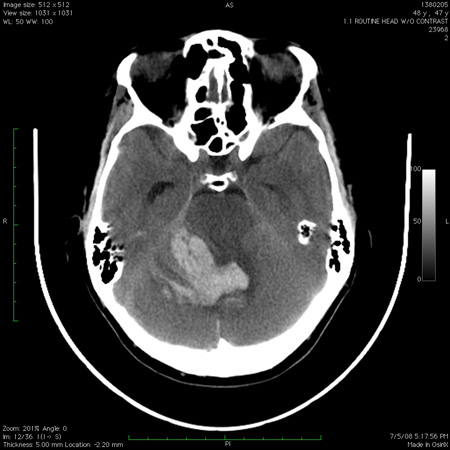

Tomografia computadorizada do cérebro mostrando hemorragia no cerebelo com extensão para o quarto ventrículo

Do acervo de Dr. S. H. Subramony; usado com permissão